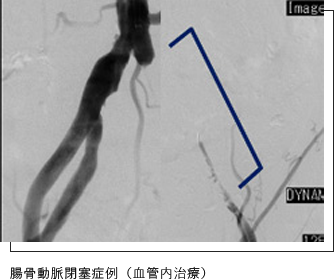

閉塞性動脈硬化症の原因は、主に「腸骨動脈」と「大腿動脈」における狭窄・閉塞に分けられます。

「腸骨動脈」の治療はほとんど血管内治療です。外科的バイパス術と比較し、治療成績は同等(スライド3)で、合併症がかなり少なくなります。

左腸骨動脈完全閉塞の患者さんですが、従来は外科的バイパス術を施行していましたが、当院ではほとんど血管内治療を施行し、成功率は95%を超えます。

腸骨動脈閉塞症例(CT angiography)

腸骨動脈閉塞症例(血管内治療)

バルーン拡張術&ステント留置術 術前